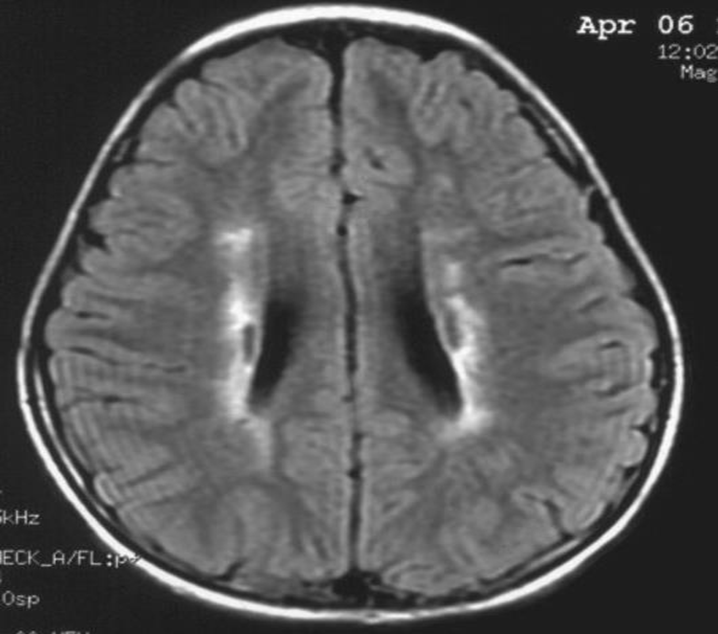

患者:林某某性別:男年齡:8 歲基本情況:出生后3個(gè)月臨床和頭部CT檢查診斷為腦癱。8年來病人曾在全國各地接受各種中西醫(yī)治療,病人入院時(shí)確診為痙攣性腦癱。治療時(shí)間:2005年7月接受干細(xì)胞移植手術(shù)。